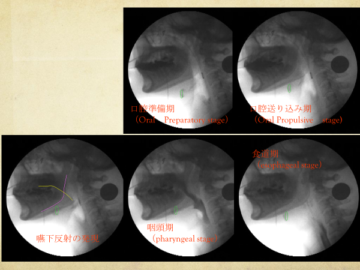

VF検査とは、造影剤入りのゼリーなどを食べてもらい、嚥下の様子をレントゲンで動画撮影します。

―VF検査―